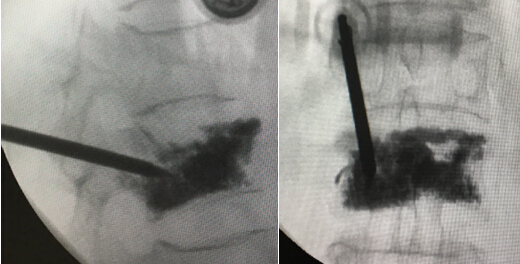

术中正侧位透视显示弯角的注射管

术中透视L1椎体骨水泥分布满意,无明显渗漏